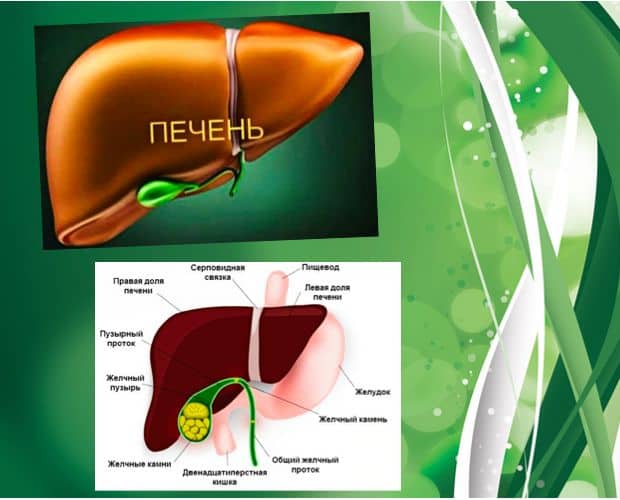

Признаки заболеваний печени: Важные симптомы и рекомендации